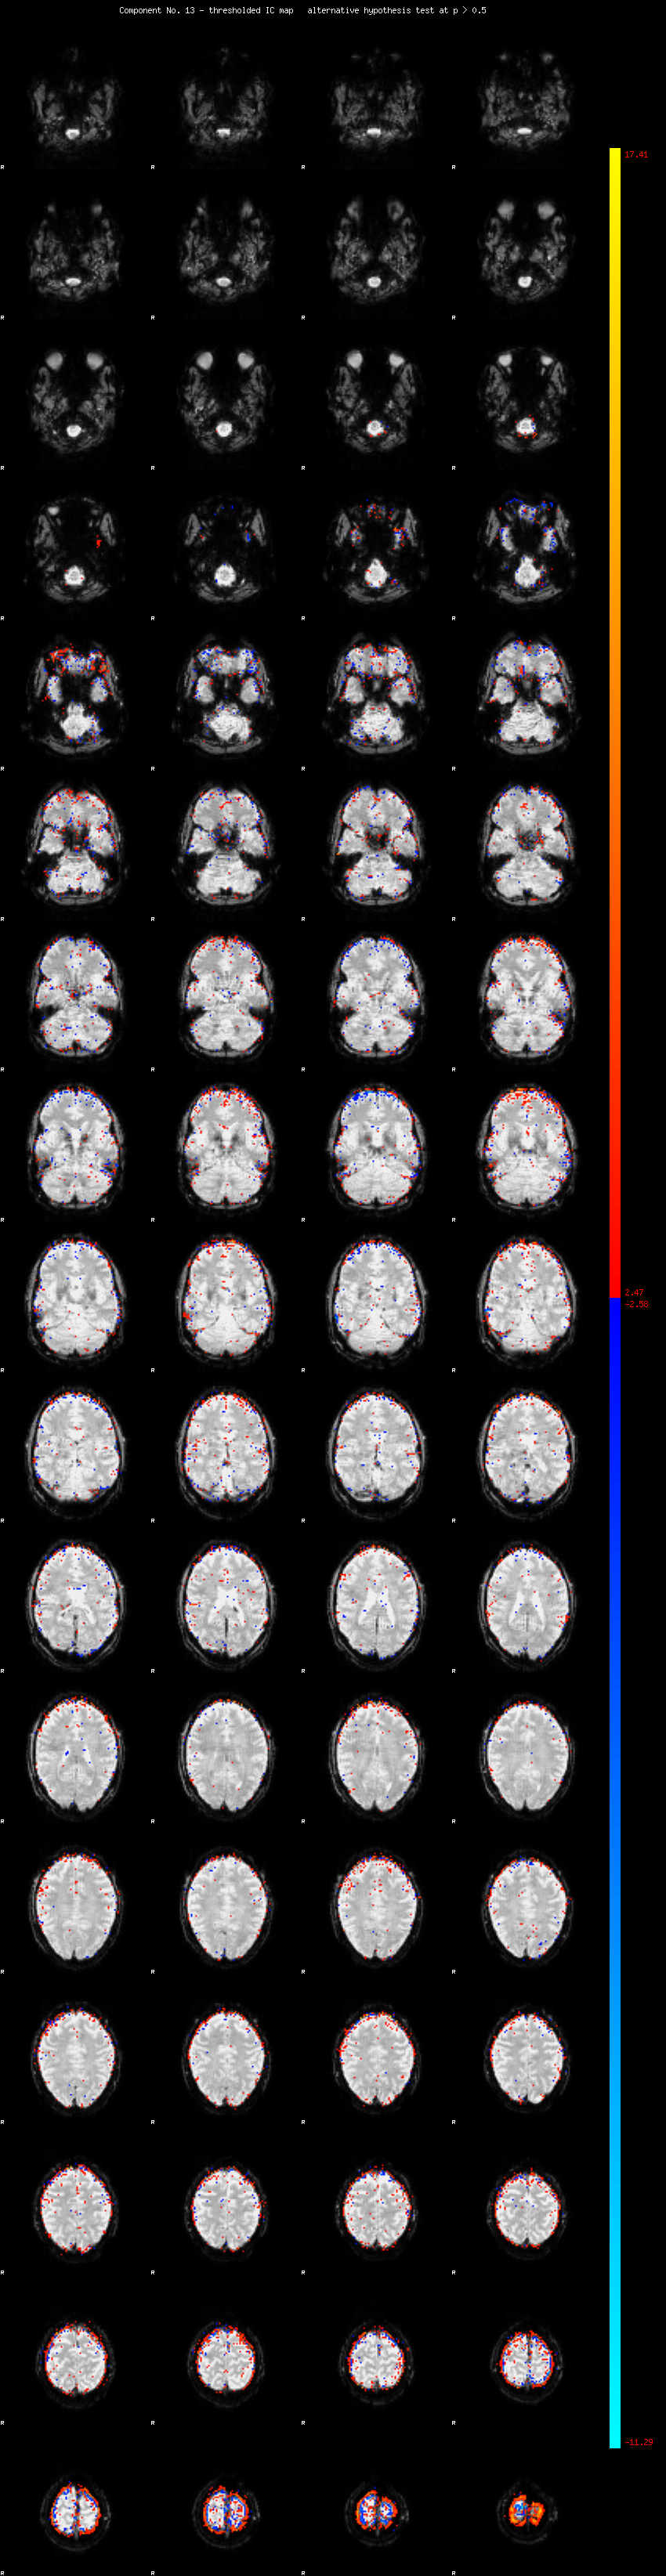

MELODIC Component 13

1.78 % of explained variance;     1.18 % of total variance

MMfit